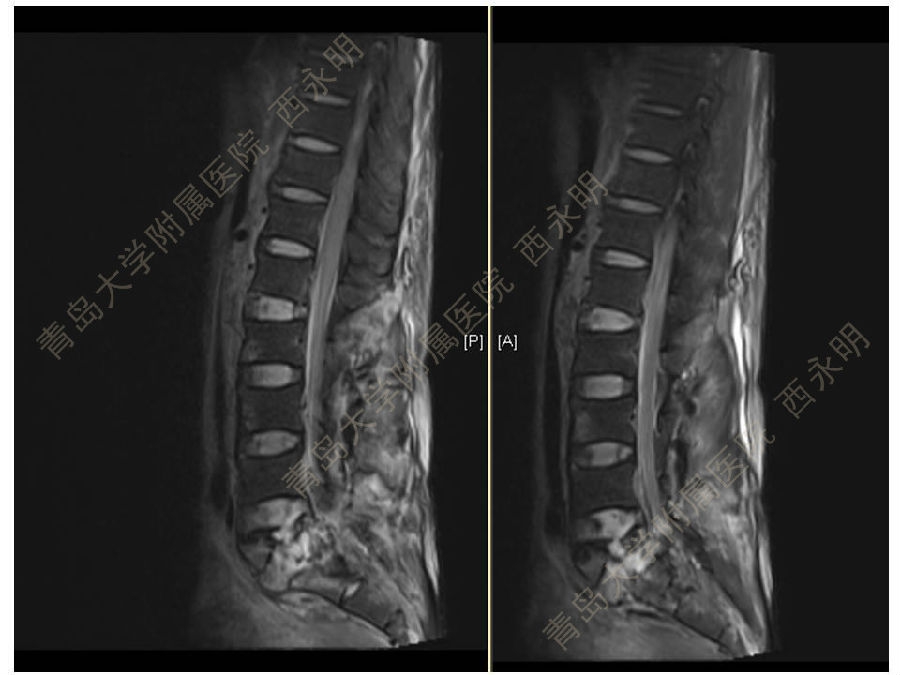

皮质骨螺钉技术及临床应用

颈椎伤病、脊柱畸形和脊柱肿瘤以及颈胸腰椎退变性疾病的微创治疗。长期从事临床一线的医、教、研工作,在多年的临床实践中积累了丰富的经验,并形成了以脊柱外科为专业方向,以颈椎外科、脊柱畸形和脊柱肿瘤为专业特色。